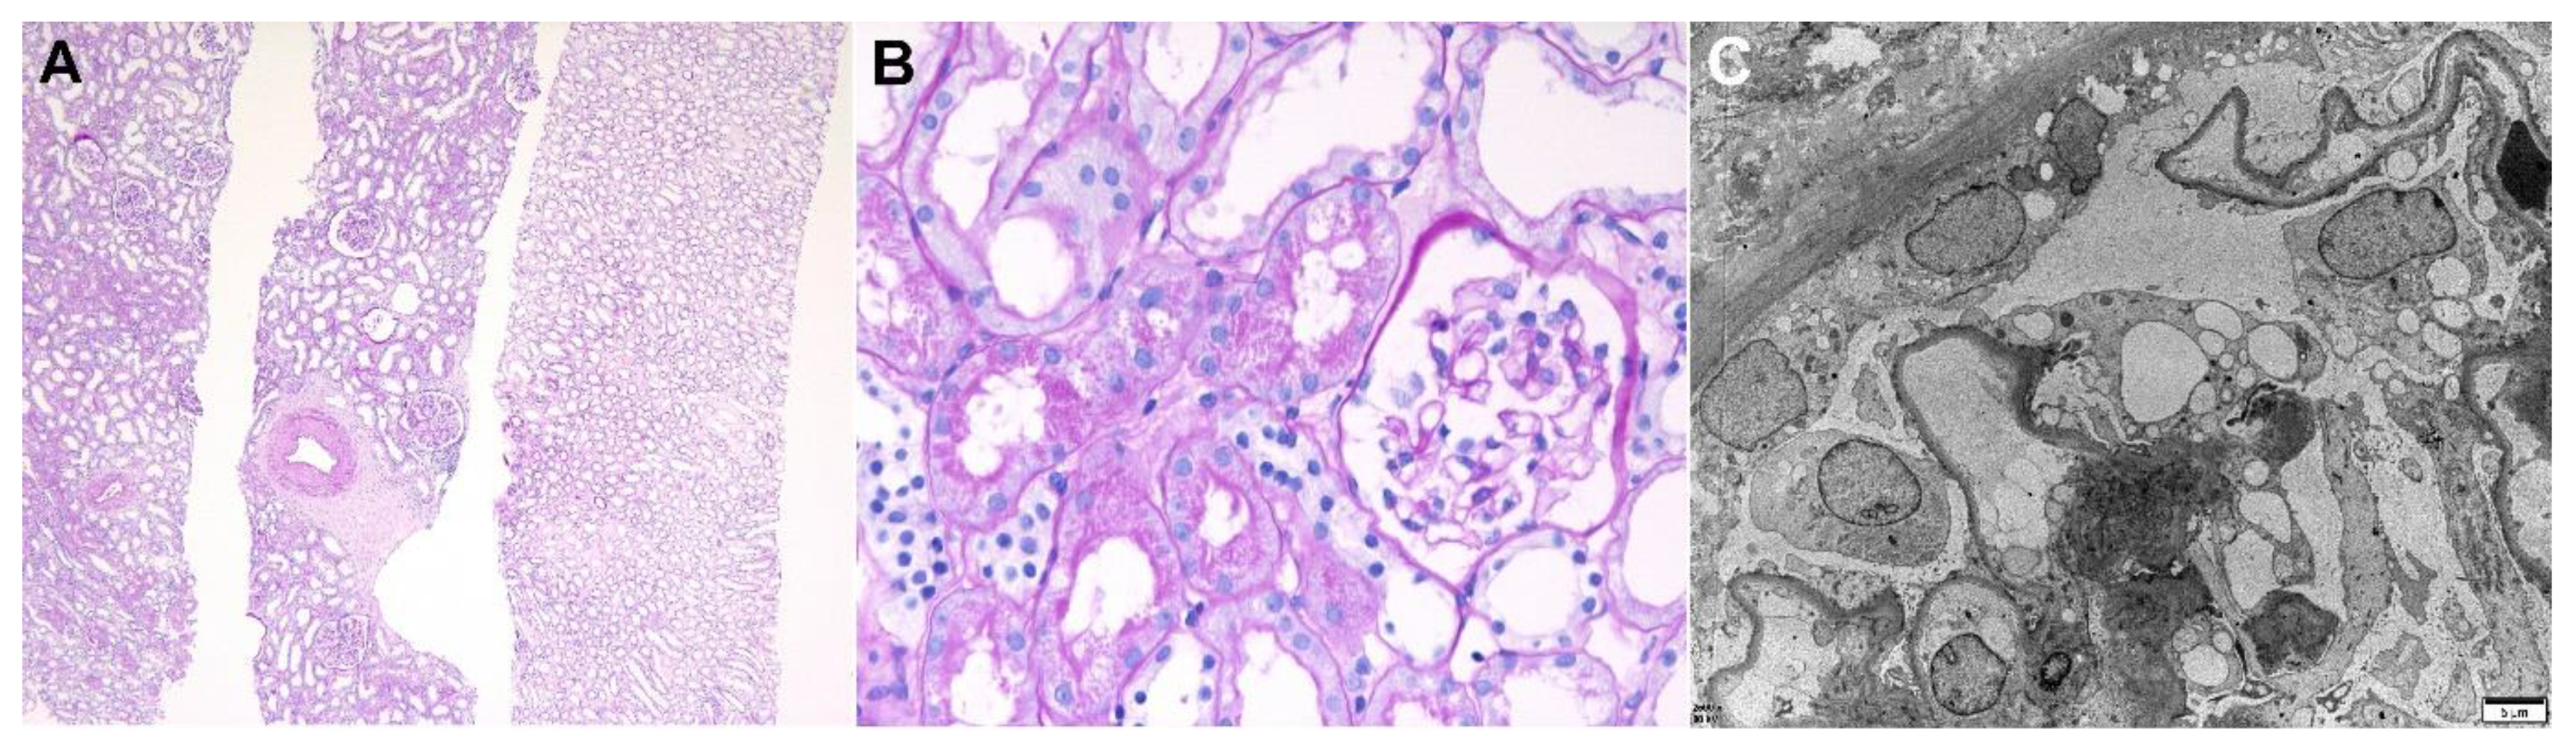

| IgA nephropathy, Haas III (M0E1C1S1T0) | 42/F | Gross hematuria | None | mRNA/ Moderna (Cambridge, MA, USA)/ 2nd | 1/54 | LM: mesangial hypercellular with increased mesangial matrix, cellular crescent, segmental sclerosis, endocapillary proliferation IF: IgA 3+, C3 1+, kappa 2+, lambda 2+ EM: many large mesangial electron dense deposits, focal foot process loss | 0.47 at 5 weeks before biopsy | 0.45 | 1.67 | RASi | PR (11 weeks) |